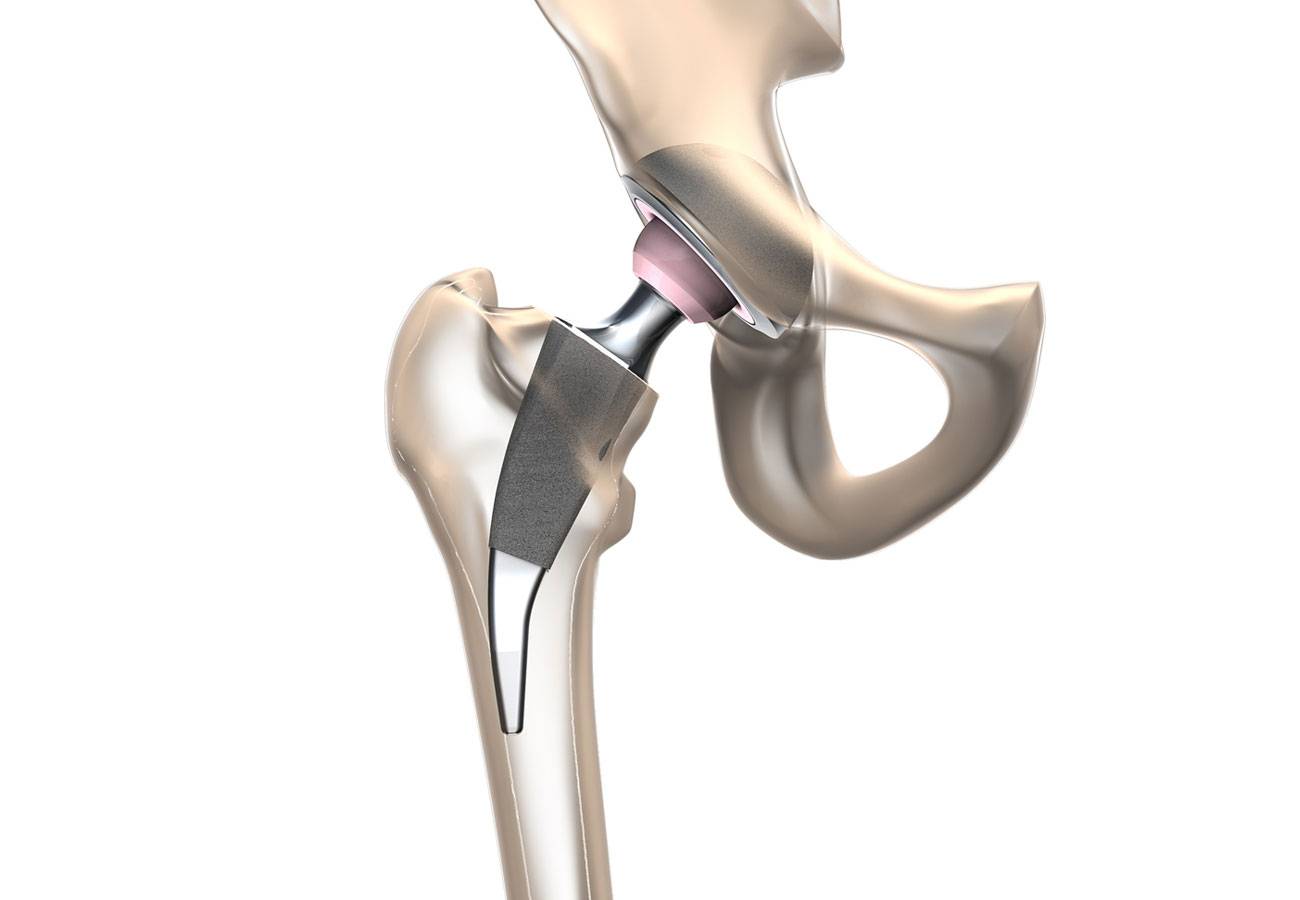

Эндопротезирование тазобедренного сустава: фото и схемы